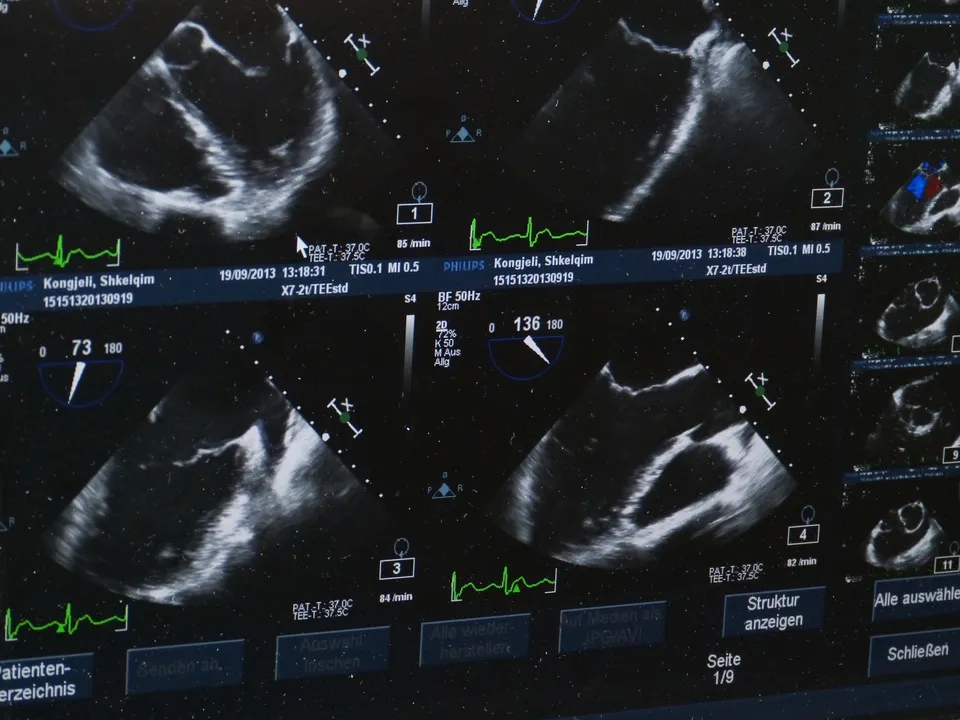

Ультразвуковое исследование почти всегда проводится при госпитализации в мытищинском НИКИ детства. Без УЗИ практически невозможно поставить верный диагноз во многих медицинских областях. Чем точнее будет картинка на экране, тем больше шансов поставить верный диагноз, именно поэтому так важно правильно подготовиться к процедуре.

Институт детства оснащен самым современным оборудованием: ультразвуковыми сканерами экспертного класса, позволяющими проводить весь спектр исследований, а также диспансерные и профилактические осмотры детей Подмосковья на самом высоком уровне. Медицинское учреждение работает в рамках государственной программы Московской области «Здравоохранение Подмосковья».

Стоит отметить, что УЗИ головного мозга, тазобедренных суставов, сердца, лимфоузлов специальной подготовки не требуют. Единственное условие — ребенок должен лежать спокойно.